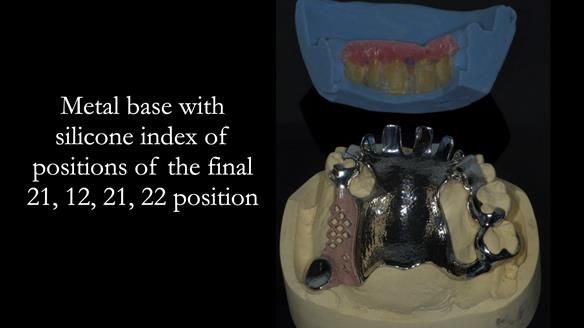

1. Denture design: A custom cobalt-chromium framework was Scandinavian-designed to maximise stability, protect the remaining teeth, and allow for future additions if needed.

Keith’s denture incorporated a Duracetal shell clasp on upper right first premolar (Myerson), which are designed to be virtually visible, providing a more aesthetic solution while enhancing patient comfort. The Scandinavian-inspired approach, based in modern removable prosthodontic techniques, ensured the denture was not only durable but also visually pleasing. Additionally, the design was carefully planned to allow for future modifications, ensuring that if Keith loses additional teeth, the denture can be adapted rather than replaced entirely.